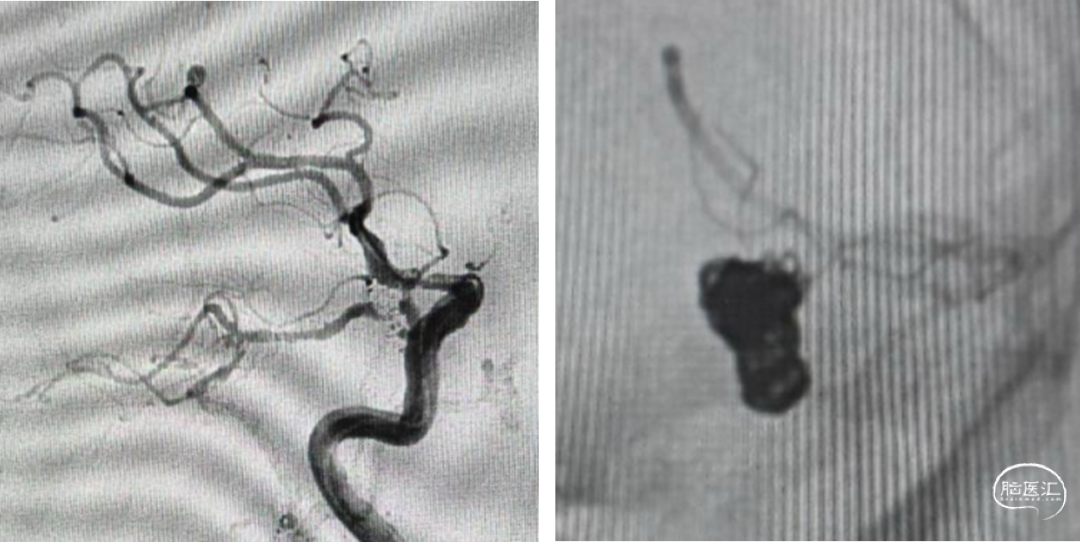

DSA:后交通动脉瘤

手术预案:后交通动脉瘤T支架辅助栓塞